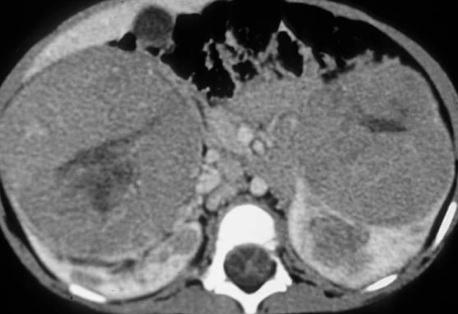

The most appropriate management of this patient with bilateral renal masses is

The next best step in management of this child with bilateral renal masses is

The guidelines from the Children’s Oncology Group call for preoperative chemotherapy when